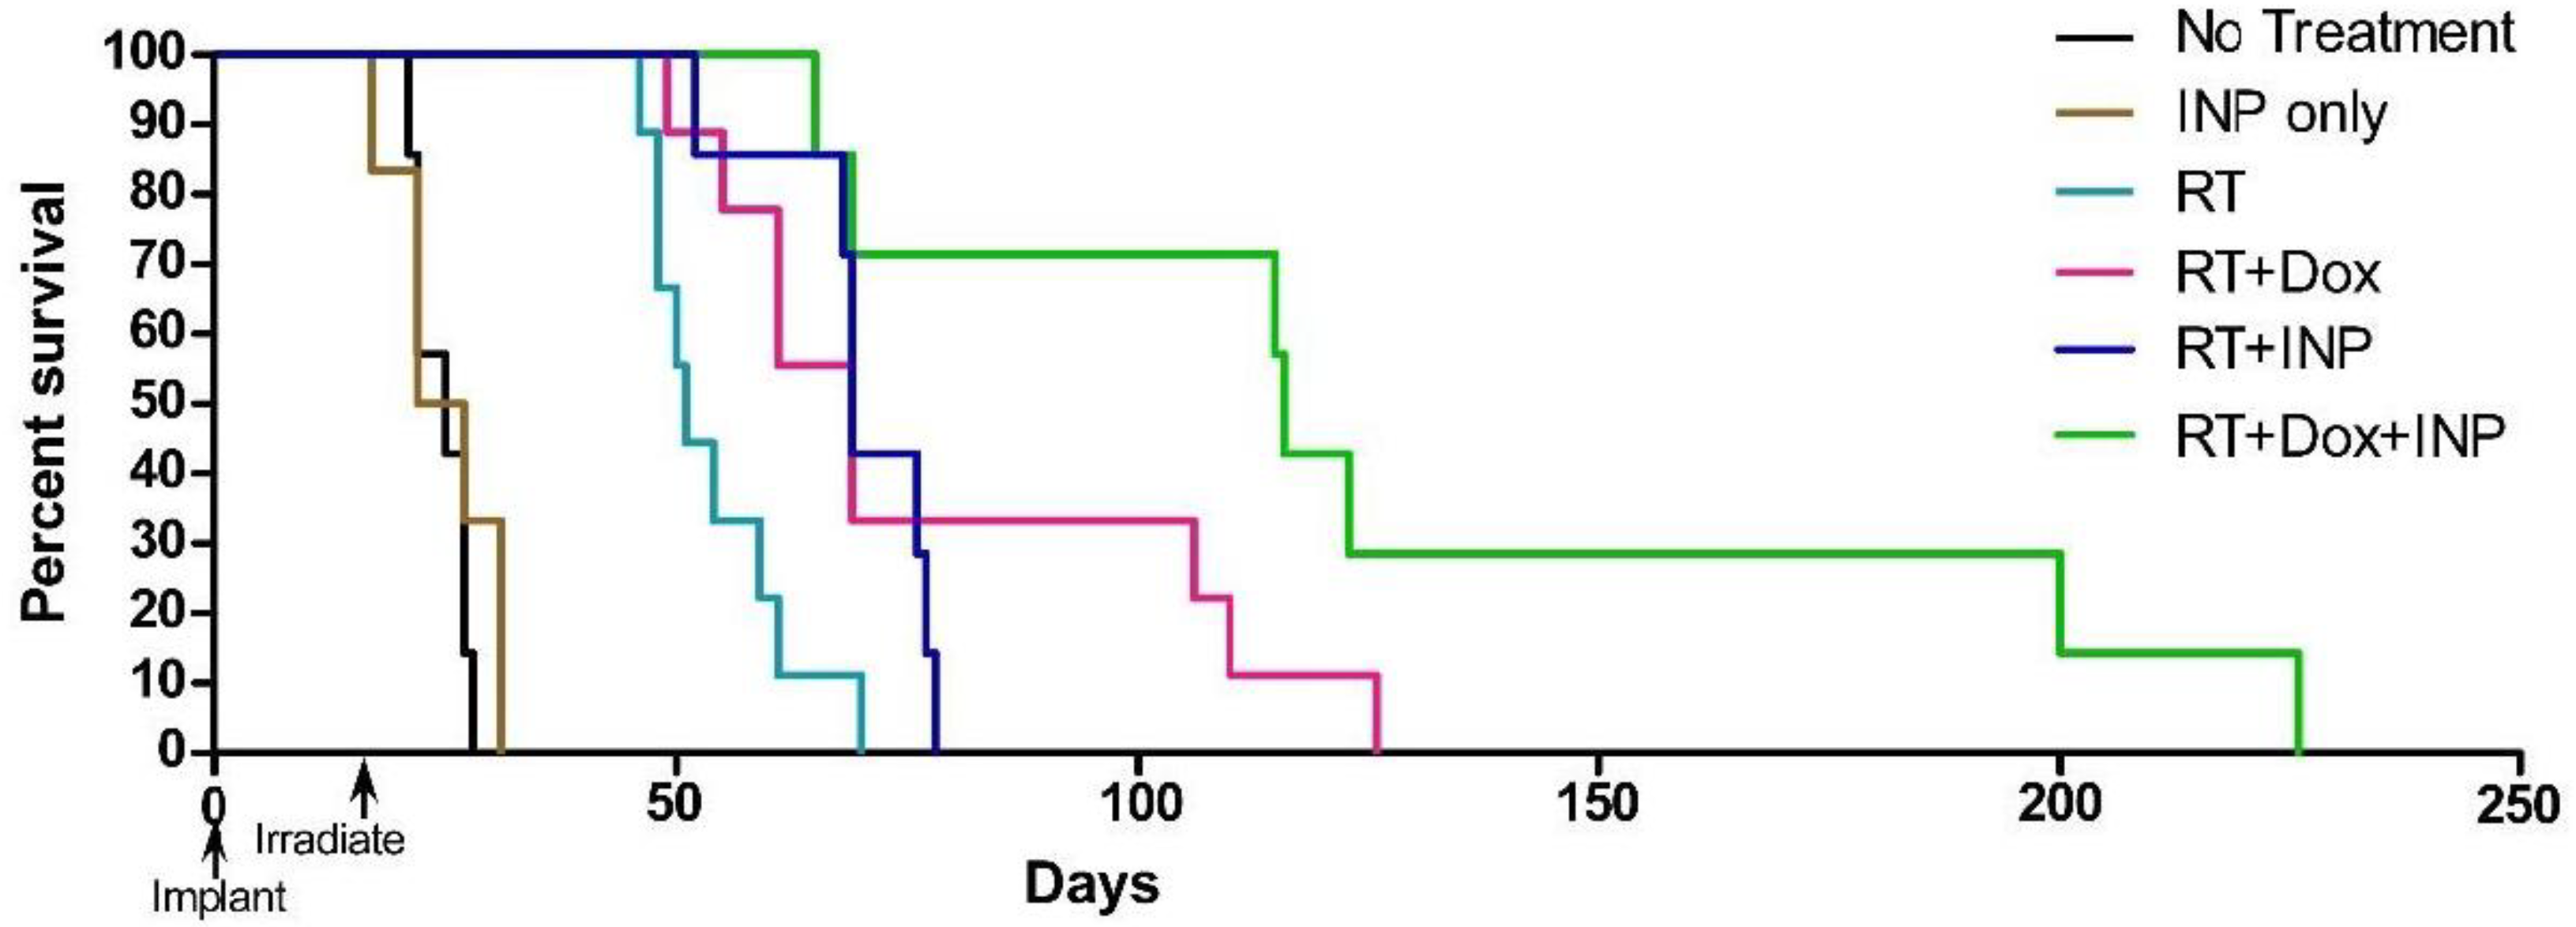

1.5. Iodine Nanoparticle Glioma Therapy

1.6. Iodine Nanoparticle Radiotherapy Synergy with Drugs